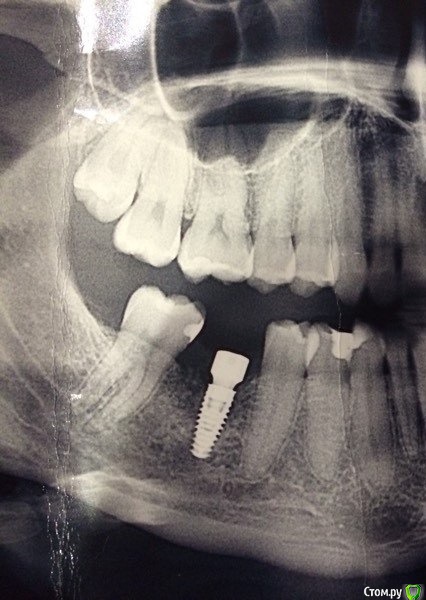

flyfli Опубликовано 7 мая, 2018 Поделиться Опубликовано 7 мая, 2018 (изменено) Техник слепил страшную постоянную коронку из циркония с 3 мя острыми буграми как у крокодила,сказав, что у меня такие зубы от природы, но от природы у меня на всех 6 ках по 2 бугра. На фото временная коронка, которая мне нравится с 2 мя буграми, можно ли просить переделать мне постоянную коронку, сделав ее такой же как временная или я не права и действительно там должно быть 3 бугра? Уважаемые стоматологи, помогите разобраться, переживаю ,что перекосит челюсть или расшатается сустав с неправильной коронкой постоянную коронку изготовили такой формы как на рисунке((( огромную и острую и с 3 мя буграми Изменено 7 мая, 2018 пользователем flyfli Ссылка на комментарий

flyfli Опубликовано 7 мая, 2018 Автор Поделиться Опубликовано 7 мая, 2018 вот такие ... мне кажется техник особо не задумываясь взял просто и слепил по первой модели, которая попалась на компюьтере или как они там моделируют это все. Ссылка на комментарий